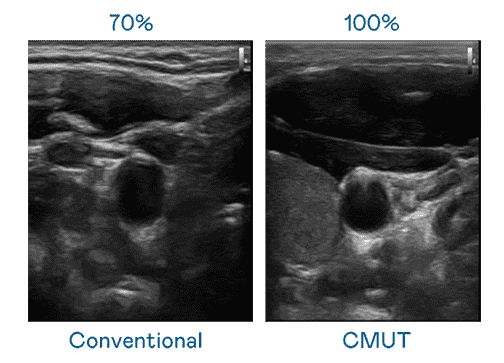

CMUT 技术是一种用电容式微机电元件来产生超音波讯号的技术。。。。与传统 PZT 压电式技术相比,,,,CMUT 频宽增加 30%,,,,更宽频的超音波讯号让影像解析度大幅提升,,,,是实现高影像品质医疗超音波扫描、、、、促进精准医疗发展的关键技术。。

大频宽带来超清晰影像

超音波影像的解析度高低,,,首先取决于探头能发出的讯号频宽。。Wepay CMUT 可提供高清晰的超音波讯号,,,,提供高频宽、、、、高灵敏度、、、、影像纹理细节更高的超音波影像,,,,协助医护人员缩短影像判读时间及利用精准的医疗影像进行诊断。。